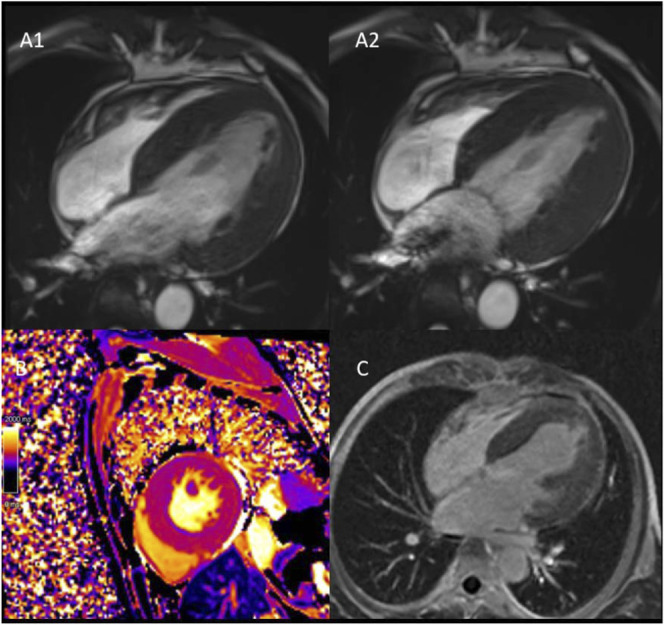

Renal, cardiac, and neurologic disease in a patient with Fabry disease, hemizygous for the c.639+5G>C intronic variant in the galactosidase alpha (GLA) gene.